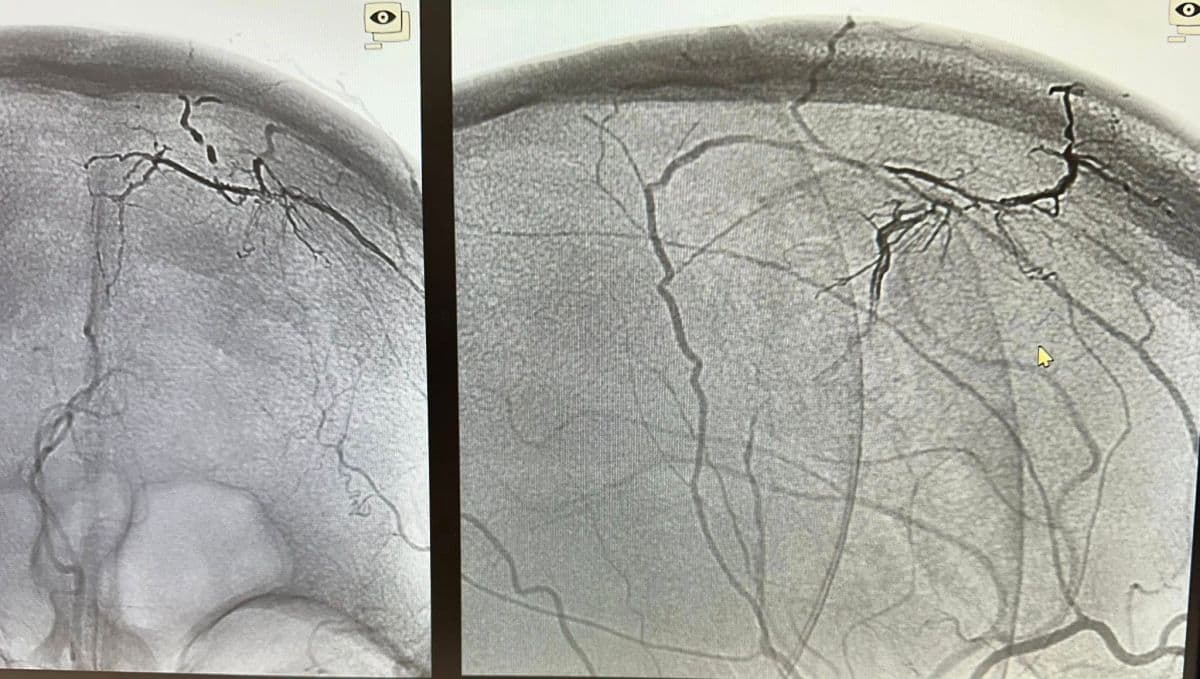

Presurgical Embolization of Brain Meningiomas reduces intraoperative hemorrhagic events and fascilitates surgical excision (Professor of Neurosurgery and Endovascular Neurosurgery V. Panagiotopoulos & Professor of Interventional Neuroradiology P. Zampakis).